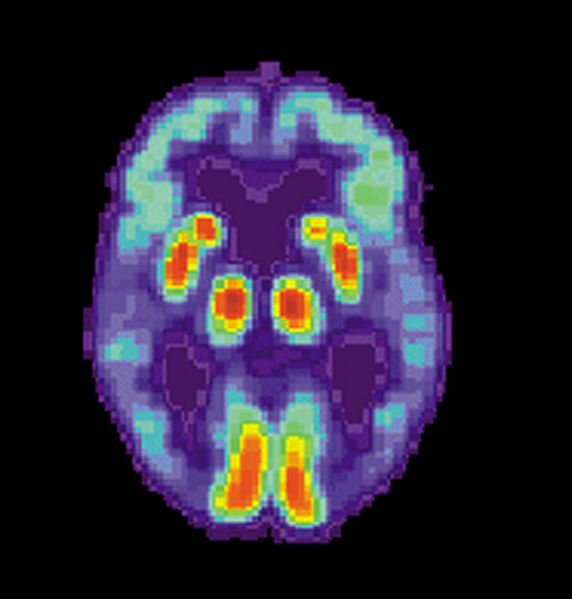

在建立最初收容前对D-10302进行的PET扫描图像

描述:SCP-1693是一种以听觉传播的阿兹海默症。感染的物理性质当前未知。其他潜在的感染源,如非言语交流,未知。以记忆删除作为治愈或缓解方法的效果未知。潜伏期未知,假说认为是在初步暴露后的3-5分钟后。